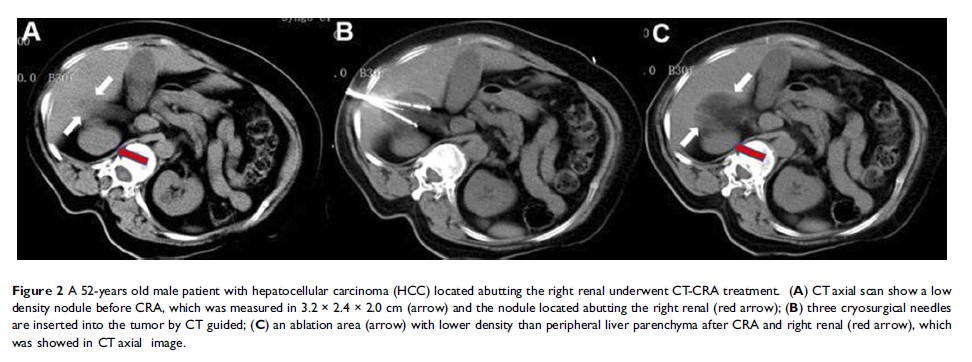

影像引导经皮微波消融与冷冻消融治疗高危部位肝细胞癌的比较:中期结果